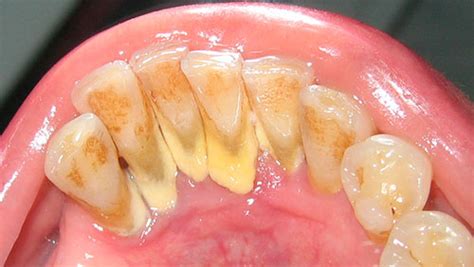

El sarro, también conocido como cálculo dental, es una concreción dura de naturaleza calcárea que se forma y deposita sobre la placa dental, adhiriéndose firmemente al esmalte de los dientes. Su coloración puede variar entre amarillenta y marrón.

La acumulación de placa bacteriana se relaciona con diferentes problemas bucodentales. Las bacterias que se acumulan en los dientes después de las comidas forman una película que se conoce como placa bacteriana o biofilm oral. Estos cálculos son sobre todo fosfato de calcio, fosfato de magnesio y carbonato de calcio. Ten en cuenta que el sarro contiene bacterias.

Se pueden diferenciar por su aspecto y ubicación:

- Sarro Supragingival: Cuando los depósitos se ubican por encima de las encías.

- Sarro Subgingival: Son aquellos depósitos que se ubican debajo de la zona gingival. Estos cálculos son de color marrón oscuro o verdoso. Es habitual que se encuentre en las zonas linguales y proximales.